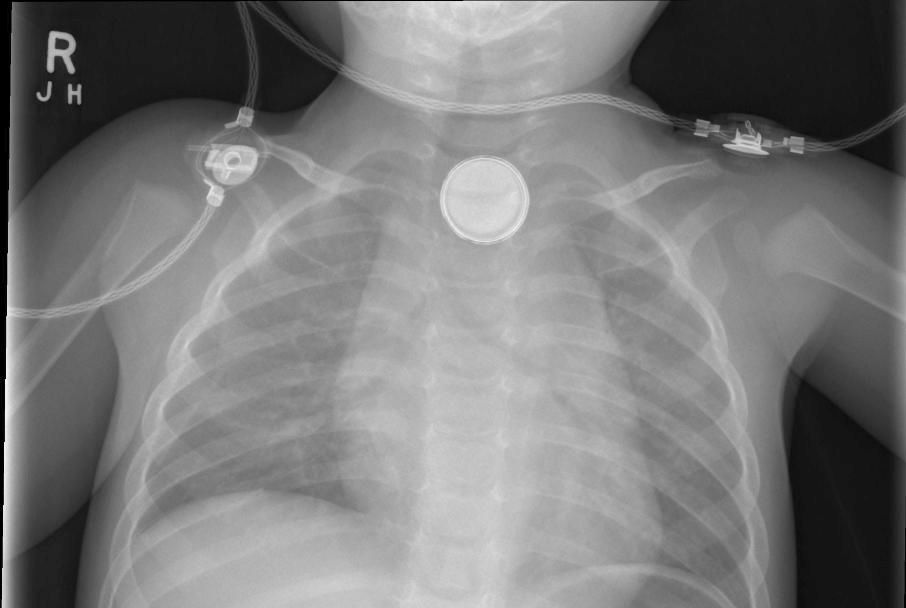

Perioperative Management of Button Battery Ingestions in Children Can A Button Battery Pass Through Batteries passing through the esophagus usually pass uneventfully through the entire digestive tract. For this reason, it’s very important to. Since button batteries are small, bright and shiny, they are very attractive to toddlers and young children. Immediate medical care is important because button batteries in the oesophagus can cause severe damage within. While most button battery ingestions are benign,. Can A Button Battery Pass Through.